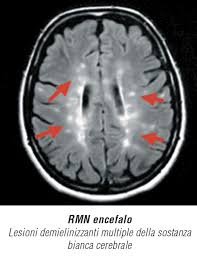

La sclerosi multipla è una delle patologie neurologiche più diffuse e allo stesso tempo più difficili da comprendere. Colpisce milioni di persone nel mondo, spesso giovani adulti, alterando profondamente la qualità della vita.

La malattia agisce attaccando il sistema nervoso centrale, compromettendo la comunicazione tra cervello e corpo.

Alla base della sclerosi multipla c’è una reazione anomala del sistema immunitario. Invece di difendere l’organismo, il sistema immunitario attacca la mielina, la guaina protettiva dei neuroni.

Questa distruzione provoca un’interruzione dei segnali nervosi, con conseguenze che possono variare da lievi difficoltà motorie a gravi disabilità.

Le ricerche più recenti hanno fatto luce su un aspetto cruciale: non è solo la mielina a essere danneggiata, ma anche i neuroni stessi.

- perdita della mielina